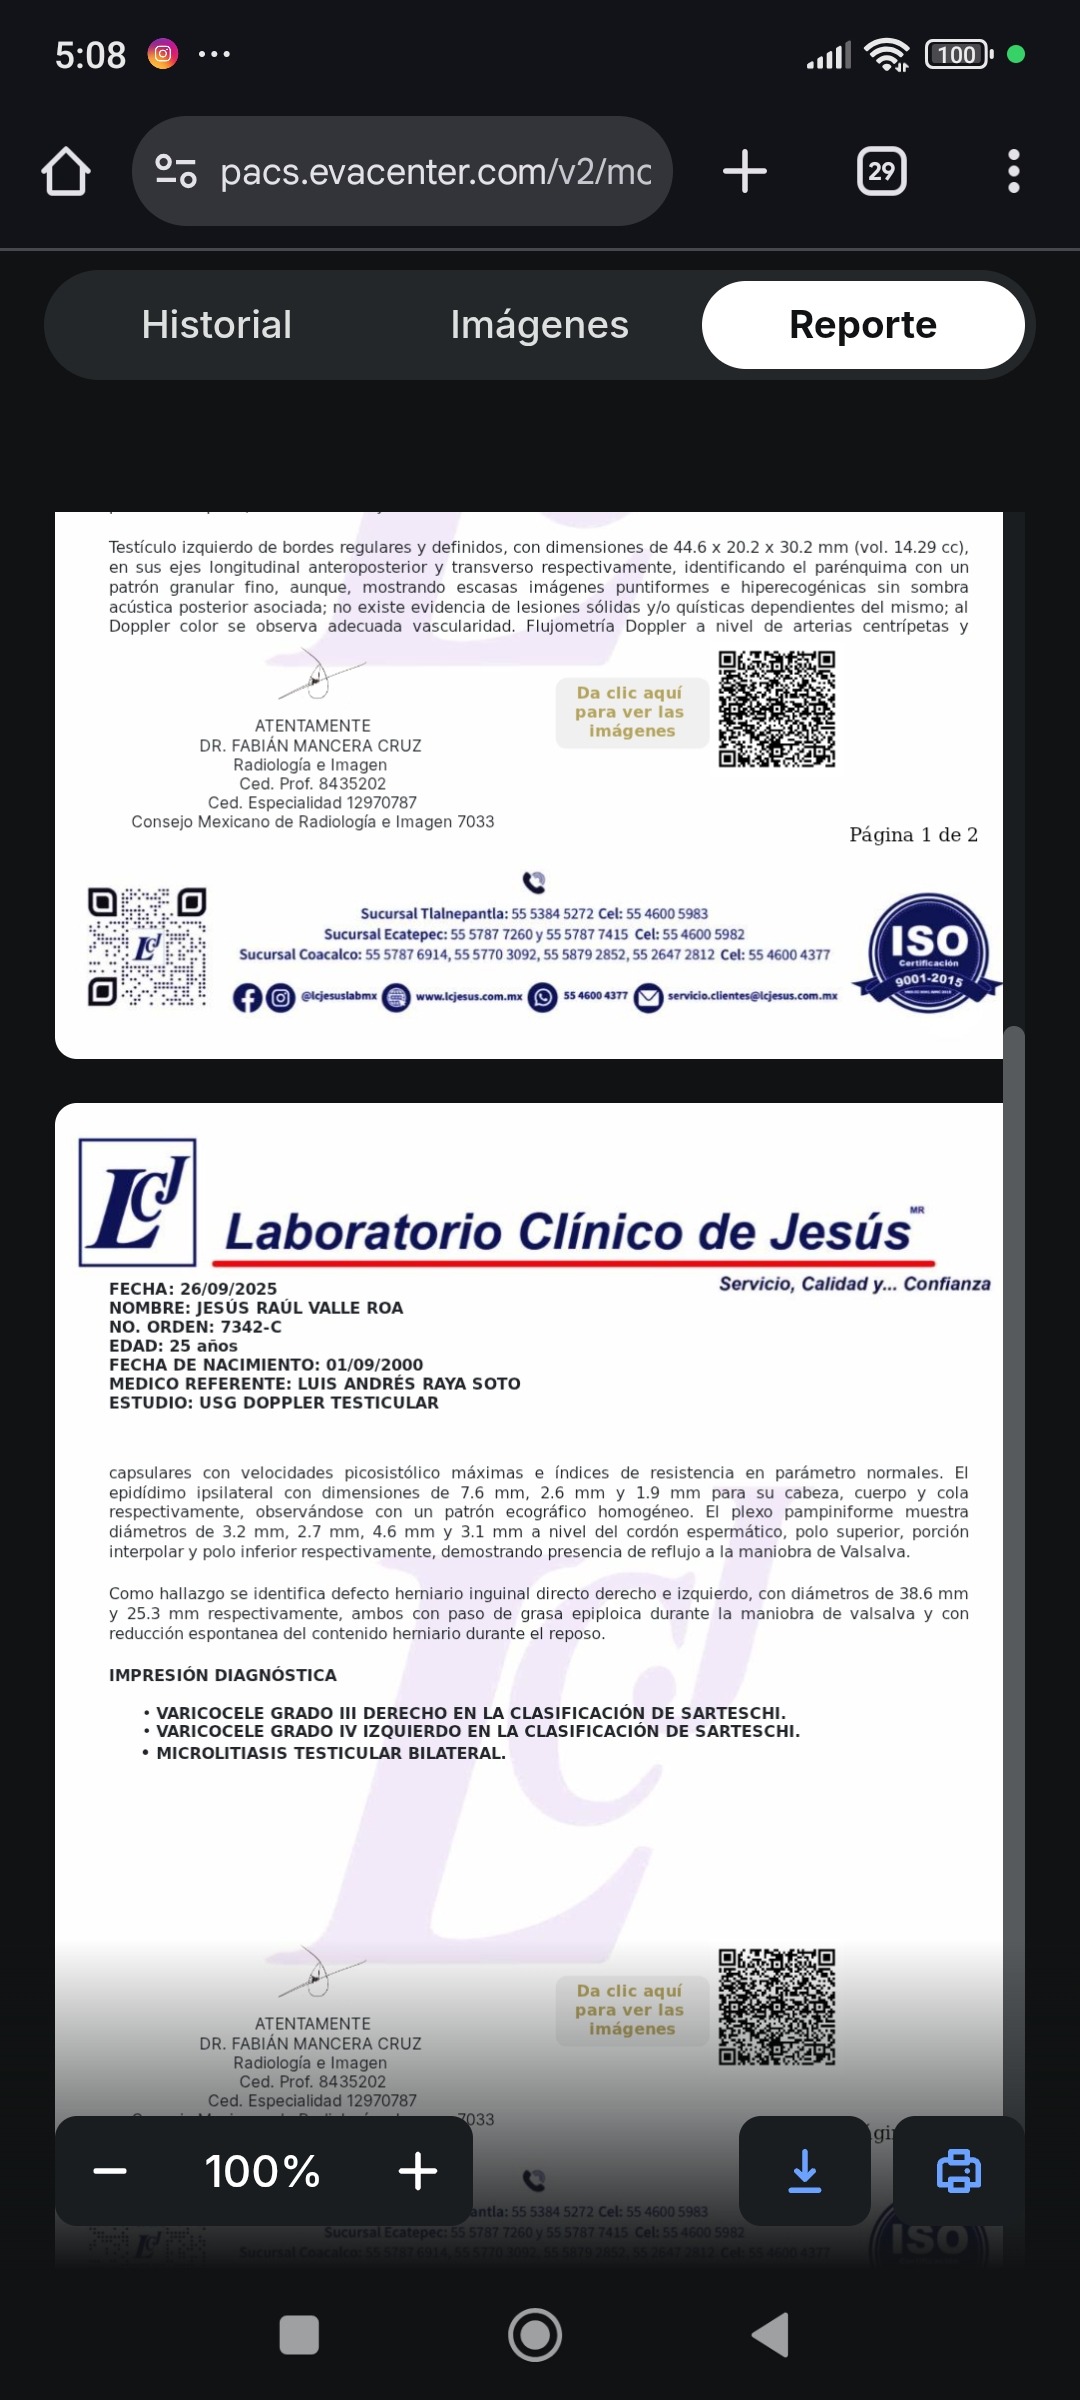

Hola me Llamo Raúl ,tengo 25 años , soy de la CDMX , me atrevo a pedir está ayuda , ya que desde hace unos meses empecé a sentir fuertes dolores en la zona de los testiculos, me hicieron estudios Doppler Testiculares, me detectaron Varicocele de Grado 4 en ambos testículos y microlitiasis testicular en ambos testículos y también tengo hernias en ambos conductos de los testiculos, sufro de fuertes dolores en ambos testículos , eso también está provocando que mi próstata este inflamada, no puedo mantenerme mucho tiempo parado o sentado, me duele mucho al orinar aveces con sangrado, llega el punto en que no puedo ya controlar la orina sale por su cuenta propia, no me atiendo en el IMSS porque el tiempo de espera es mucho , fui a médico particular y me dijeron que ya era urgente la operación porque la sangre no está llegando a los testiculos y se están muriendo, en estos momentos corro riesgo de Esterilidad , y las hernias si no se tratan pueden abrir mas y provocar que los intentos bajen por los conductos de los testiculos y sea una urgencia muy grava y riesgo de una extirpación del intestino si eso llega a pasar , pido su ayuda para poder llegar a esta cantidad, ya que en mi situación es muy difícil poder conseguir todo el dinero.